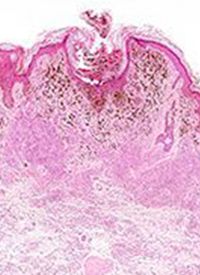

The tumor weight and volume were decreased in the combination cohort vs the other groups, with no significant change occurring in the body weight of the mice. Real-time PCR analysis of the treated tumors demonstrated reduced GDF15 and IL6 mRNA expression in the NHWD-870 and combination cohorts, and immunohistochemistry (IHC) staining showed decreased protein levels of GDF15, p-STAT3 (Y705) and p-STAT3 (S727) in these cohorts.

In addition, IHC staining for Ki67 showed fewer proliferative cells in the combination cohort, and a TUNEL assay showed that this cohort had an increase in the number of apoptotic cells. These findings indicate the synergy between BET inhibitors and sunitinib for inducing in vivo tumor suppression.